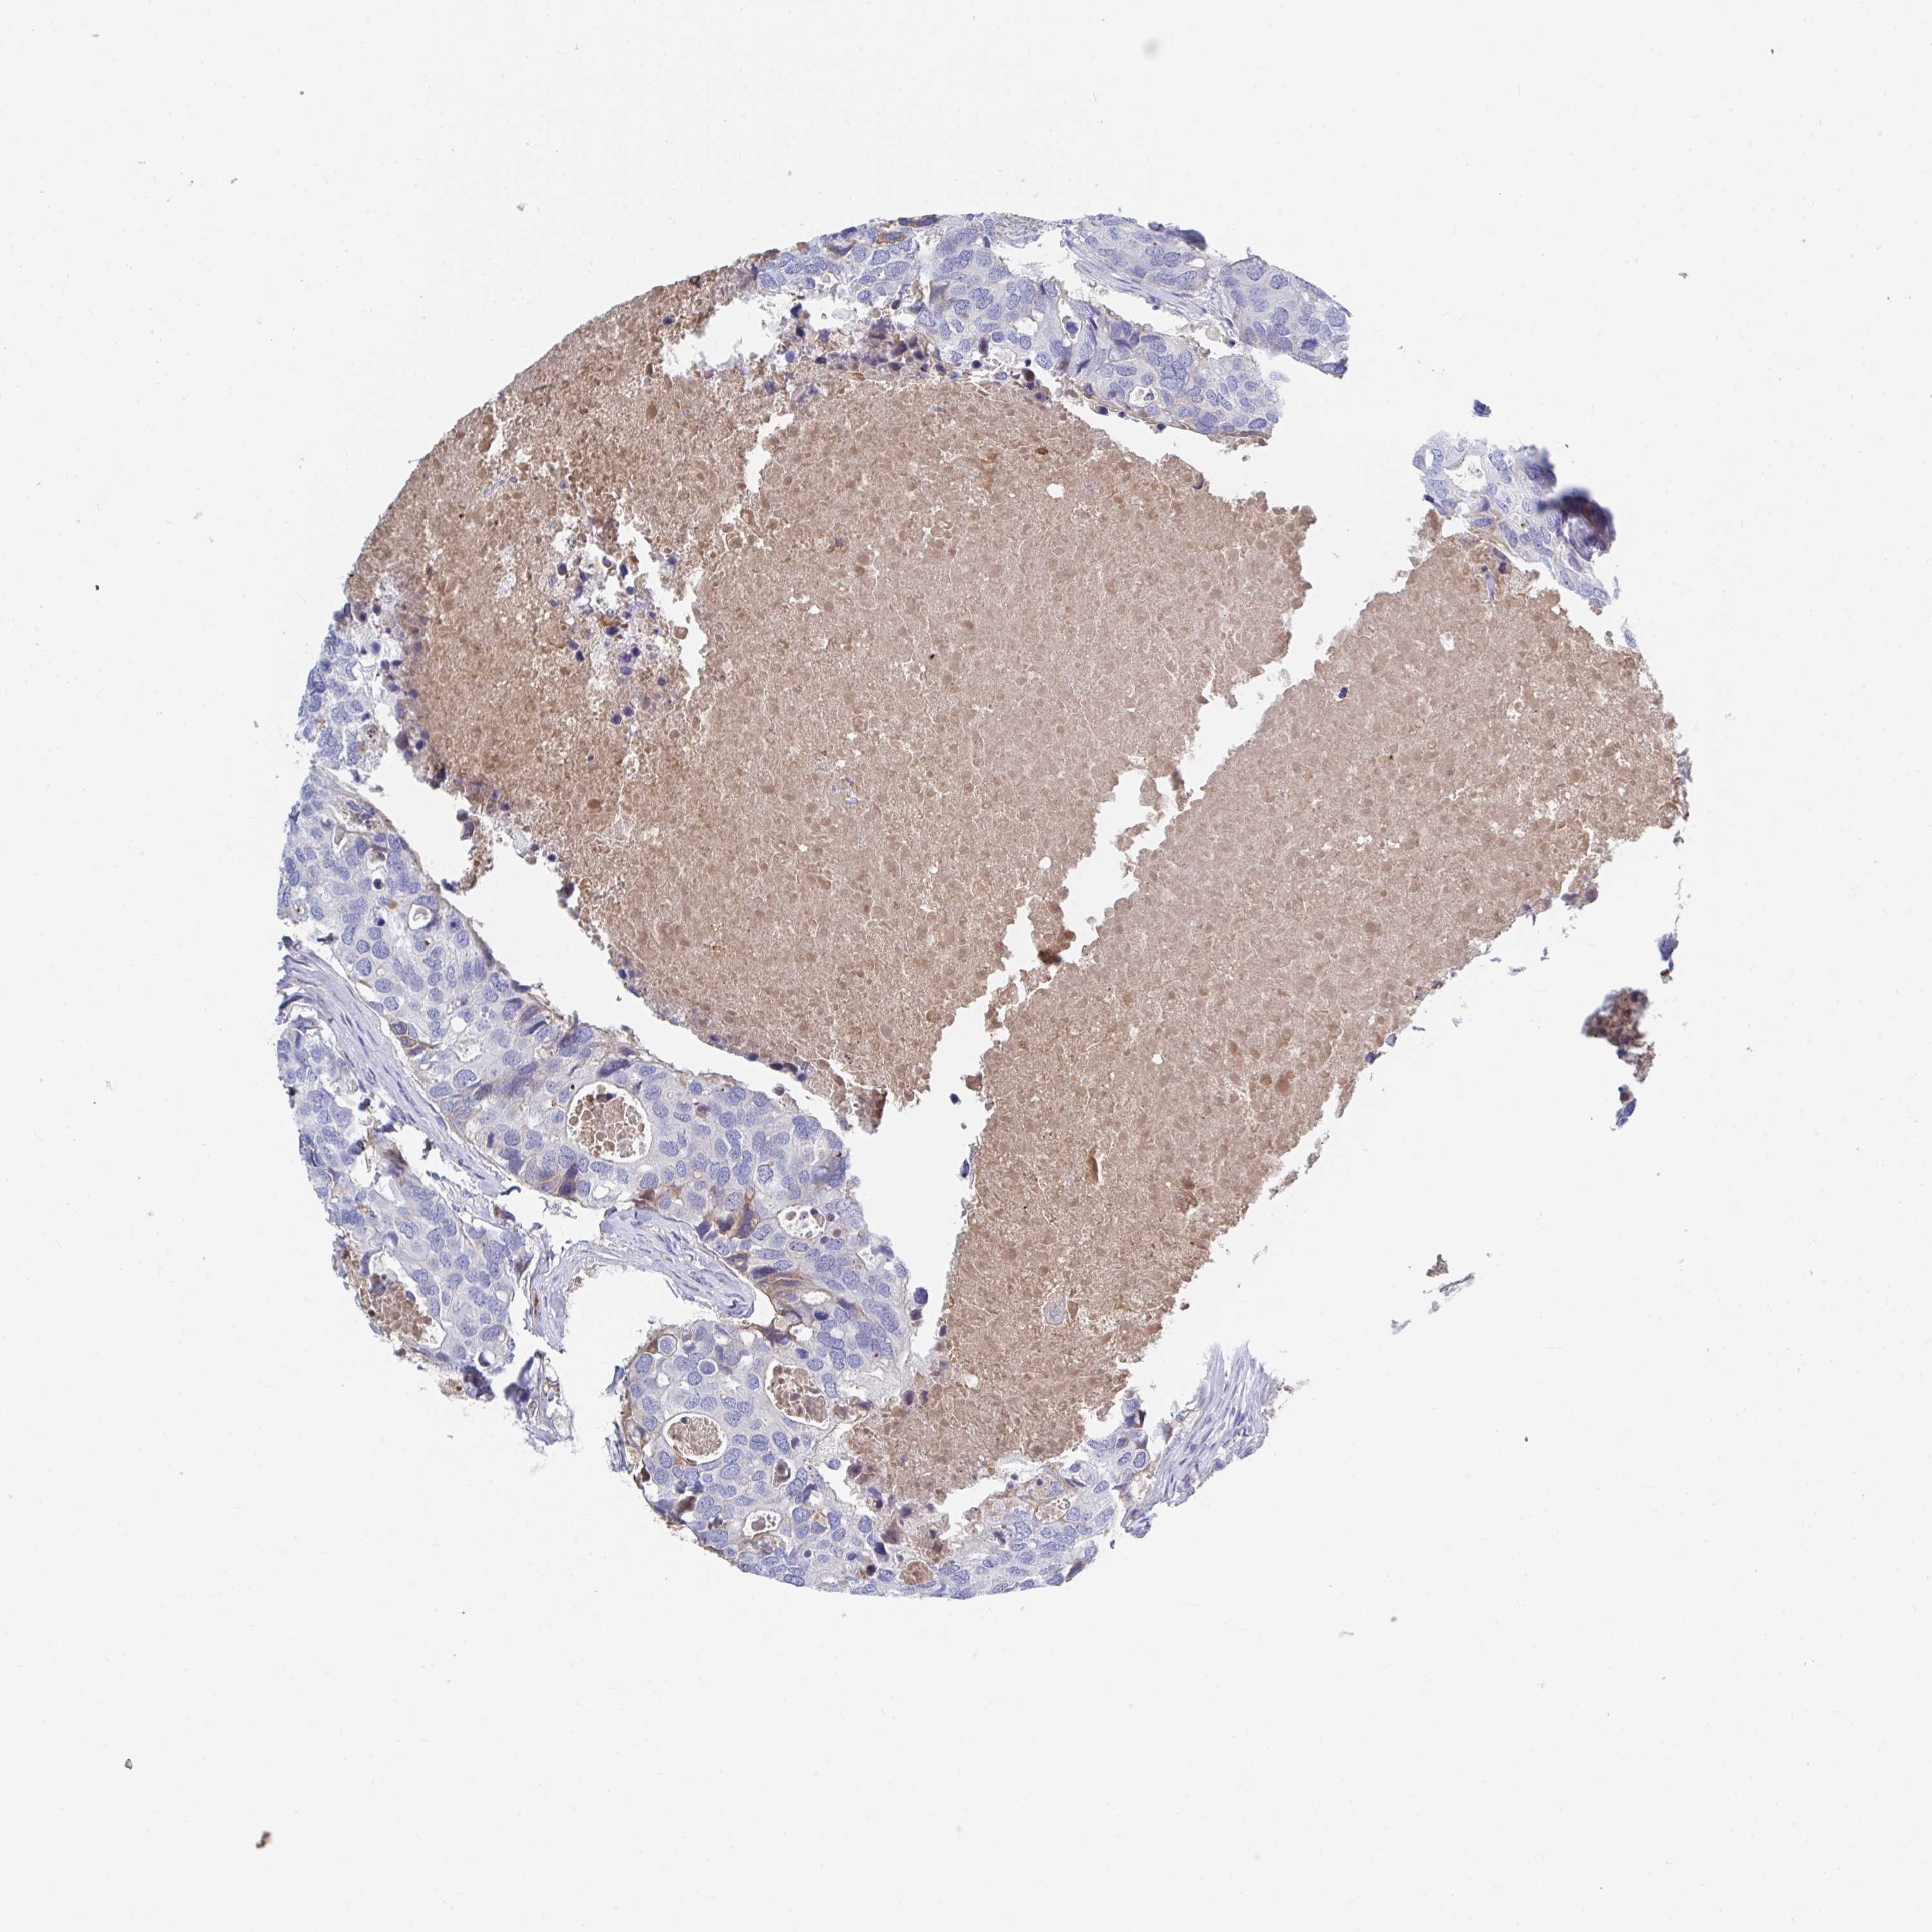

BRCA TCGA BRCA VALIDATION PROTEIN EXPRESSION

Breast cancer

Human cancer

TNFAIP6 is not prognostic in Breast Invasive Carcinoma (TCGA)